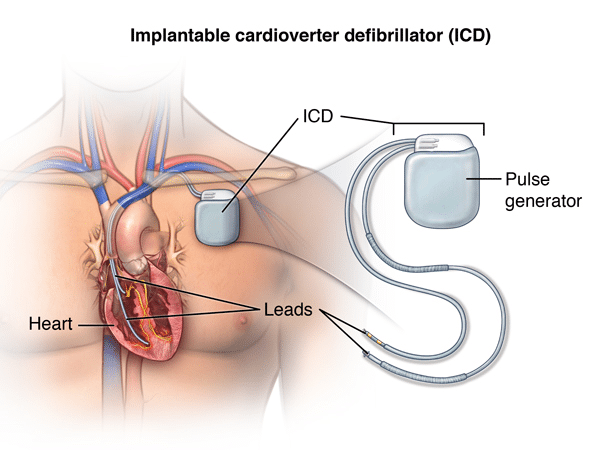

Overview

Package includes:

Days in hospital : 3 Days (For patient and one attendant)

Days in hotel : 10 Days (For patient and one attendant)

Room type in hospital : Shared

Room type in hotel : Private

Hotel category: Standard

Value added benefits of the ICD:

Ø Doctor consultation charges

Ø Lab tests and diagnostic charges

Ø Room charges inside hospital during the procedure

Ø Surgeon Fee

Ø Nursing charges

Ø Hospital surgery suite charges

Ø Anesthesia charges

Ø Routine medicines and routine consumables (bandages, dressings etc.)

Ø Food and Beverages inside hospital stay for patient and one attendant.

Extra benefits:

ü Interpreter

ü Visa assistance

Ø Site tourism of the city

Ø Follow up with the doctor

Ø Airport pick up and drop

Ø Free online consultation with the doctor

Ø Priority appointments with the doctor

Ø Room upgrade from sharing to private

Overview

Package includes:

Days in hospital : 3 to 4 Days (For patient and one attendant)

Days in hotel : 12 Days (For patient and one attendant)

Room type in hospital : Shared

Room type in hotel : Private

Hotel category: Standard

Value added benefits of the AICD Implantation:

Ø Doctor consultation charges

Ø Lab tests and diagnostic charges

Ø Room charges inside hospital during the procedure

Ø Surgeon Fee

Ø Nursing charges

Ø Hospital surgery suite charges

Ø Anesthesia charges

Ø Routine medicines and routine consumables (bandages, dressings etc.)

Ø Food and Beverages inside hospital stay for patient and one attendant.

Extra benefits:

ü Interpreter

ü Visa assistance

Ø Site tourism of the city

Ø Follow up with the doctor

Ø Airport pick up and drop

Ø Free online consultation with the doctor

Ø Priority appointments with the doctor

Ø Room upgrade from sharing to private